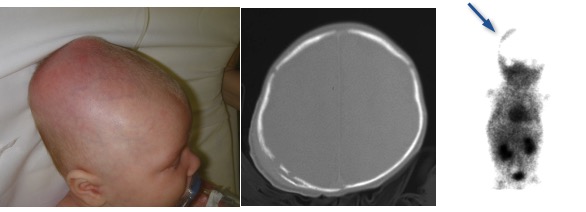

dans de rares cas,le céphalhématome est bilatéral, séparé en 2 par l’adhérence du périoste à la suture sagittale. on parle alors de crâne natiforme (du latin nates, les fesses)

on le différencie de l’hématome sous-galéal par le fait qu’il est limité par les sutures crâniennes.

un céphalhématome bilatéral témoigne de l’absence de la suture sagittale, et est donc pathognomonique de la scaphocéphalie.